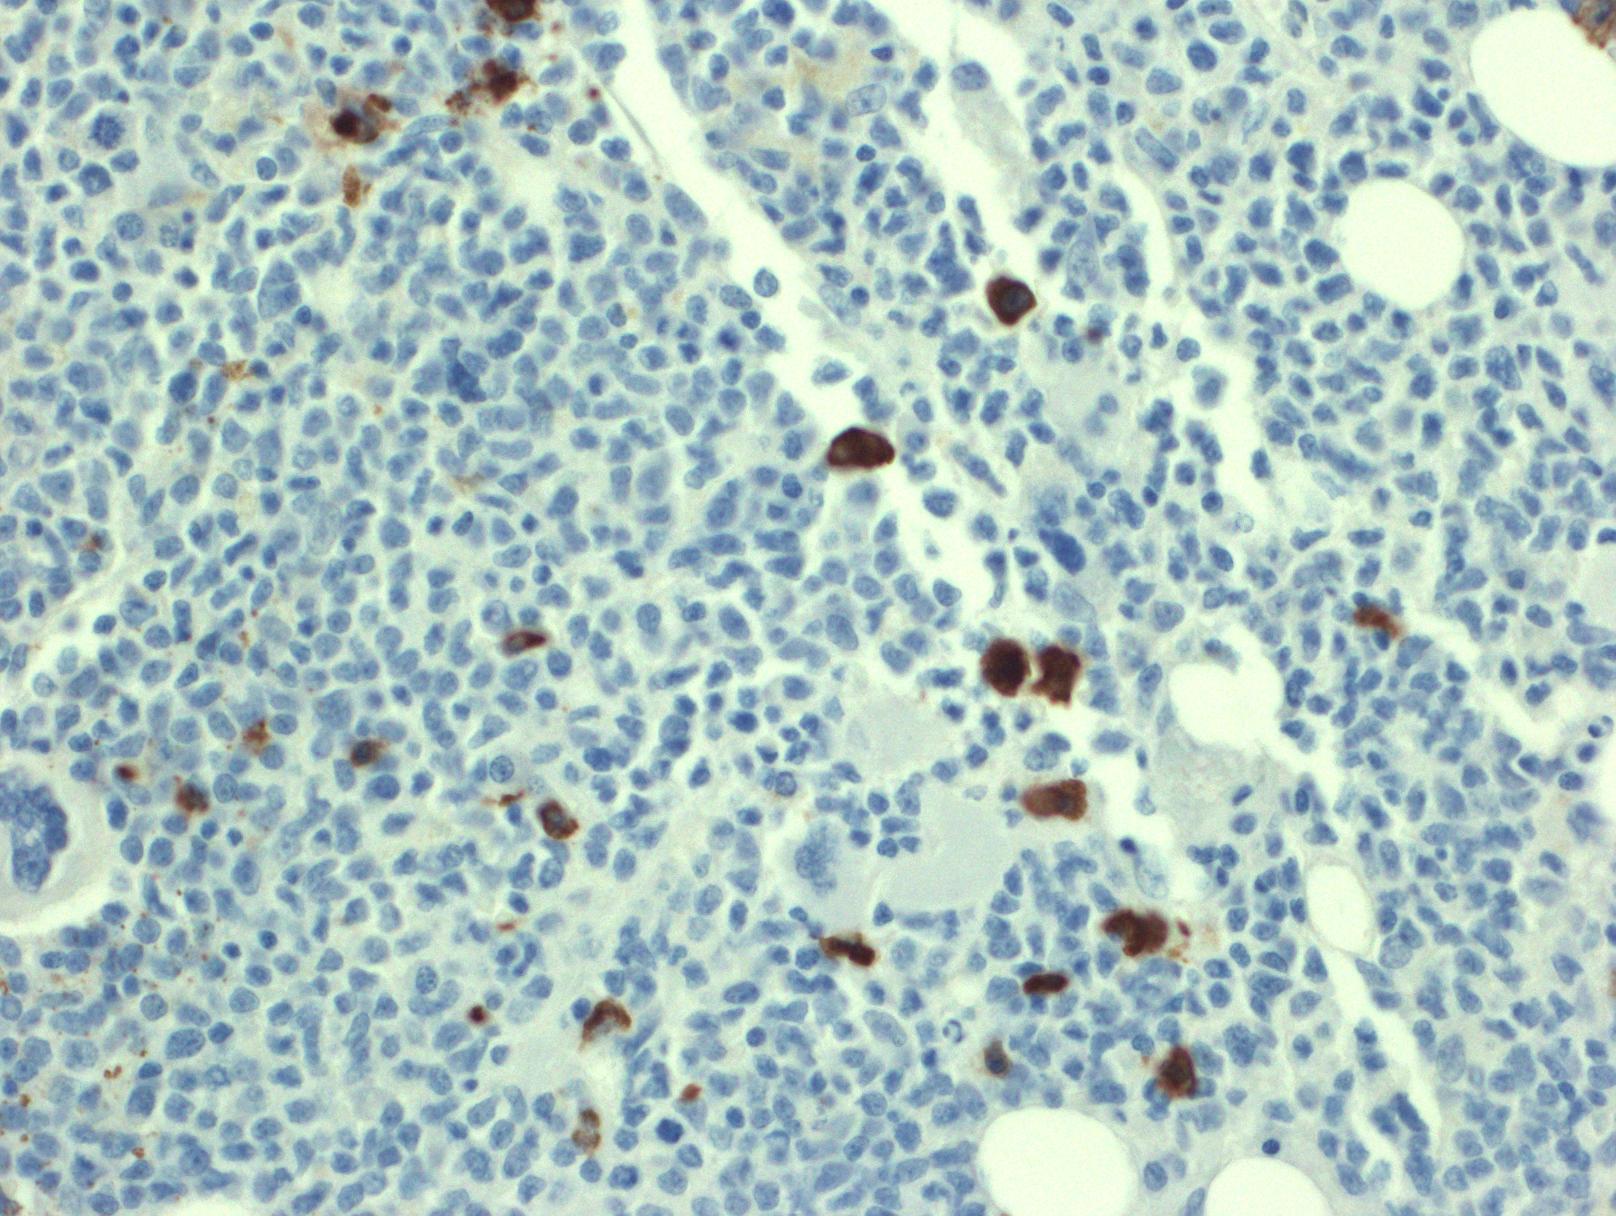

- 免疫表型: T-ALL/LBL 中淋巴母细胞呈 TdT 阳性,可表达 CD1a、CD2. CD3. CD4. CD5. CD7 和 CD8 中的一种或多种,最常见的是 CD7 和胞浆 CD3ε 阳性表达,其中只有 CD3 具有确定肿瘤细胞来源的特异性。CD4 和 CD8 常有合表达,CD10 也可以阳性;但这些都不具特异性。不成熟抗原除 TdT、CD1a、CD34 外,CD99 的表达也可表明其前体细胞的特性。部分病例表达 TAL1(核染)。偶有病例 CD117 阳性(常伴有 FLT3 突变)。10%病例表达 CD79a,少数可以表达 CD13 和/或 CD33。根据分化阶段不同,可将 T-ALL 分为以下几型:原 T(Pro-T):cCD3+、CD7+、CD2-、CD1a-、CD34-/+、CD4-、CD8-;前 T (Pre-T):cCD3+、CD7+、CD2+、CD1a-、CD34+/-、CD4-、CD8-;皮质 T(cortical T):cCD3+、CD7+、CD2+、CD1a +、CD34-、CD4+、CD8+;髓质 T(medullary T):cCD3+、CD7+、CD2+、CD1a-、CD34-、sCD3+、CD4 或 CD8 阳性。前两型中的很多病例符合 WHO 2017 年版分类中的早期前 T 淋巴母细胞白血病 (见下)。